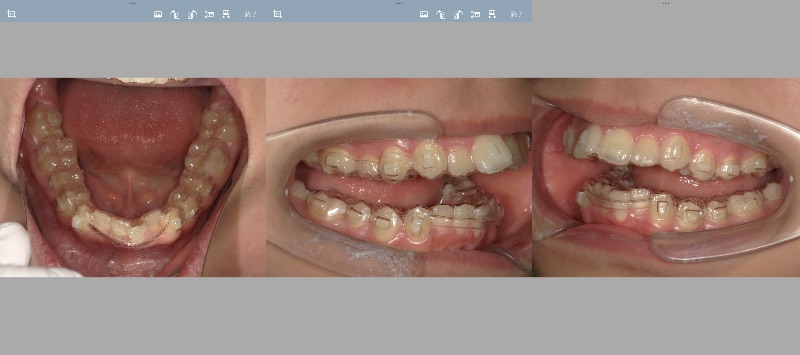

- Qクリンチェックの修正小児矯正

Oさん小学生

治療方針、クリンチェックご指導下さい - A正規会員もしくはQAアクセス会員になると、Aが表示されます。